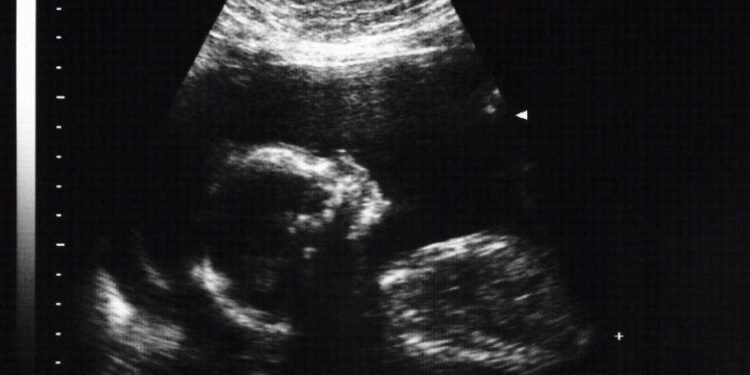

To do this, first an ultrasound is done to locate the embryo in the uterus. After about twenty milliliters will be extracted, that is, a little liquid. Local anesthesia is not used in this procedure, although a cream can be used to numb the area.

The fluid is obtained through a puncture with a fine needle that is inserted through the abdominal wall and the uterus. While the puncture is being performed, an ultrasound is performed so that the extraction of the liquid is correct. This procedure usually lasts 20-30 minutes and you may feel a sting or pressure during the test, although you may not feel any pain.